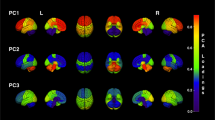

Definition of region of interest

We selected regions of interest (ROIs) using all 90 Automated Anatomical Labeling (AAL)44 map labels, as shown in Fig. 1. (For labels and details, please refer to Supplemental Table S4).